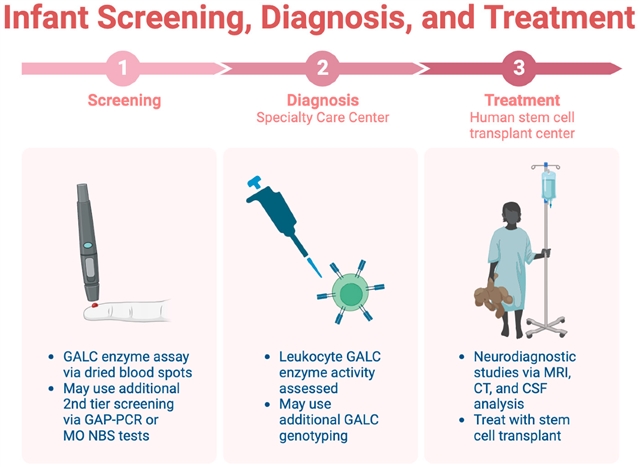

3. 克拉伯病(球形细胞脑白质营养不良)

GALC 基因突变致病,婴幼儿期发病凶险。

• MRI 特征:丘脑、皮质下白质异常信号,婴儿型可见视神经与颈髓膨大。

• 辅助检查:脑脊液鞘氨醇蓄积,新生儿筛查是干细胞移植获益的关键。

婴幼儿川崎病筛查的三步流程